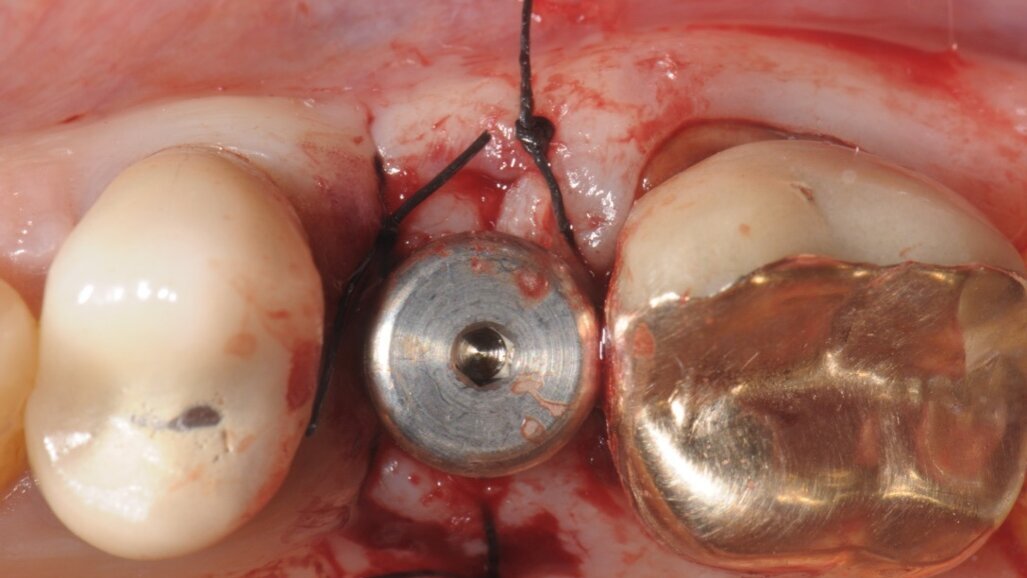

La paziente di 55 anni, non fumatrice, non affetta da alcuna patologia sistemica, da noi trattata con una procedura implantare sostitutiva dell’elemento naturale si era presentata alla nostra osservazione al fine di poter valutare un dolore riferito in sede 2.5 di tipo continuativo tollerabile ma con scarse variazioni di picco algico. L’elemento era stato curato endodonticamente e protesicamente da meno di 1 anno. All’esame obiettivo si presentava una neo protesizzazione individuale su 2.4 e 2.5, mentre su 2.6 si presentava una pregressa protesizzazione in oro-resina con vistosa retrazione gengivale che scopriva un margine corono-protesico impreciso. Il dolore riferito si estendeva tra i 2 premolari in oggetto. Al sondaggio si evidenziava un tragitto patologico di 9 mm in sede mesio-vestibolare della corona in 2.5 (Fig. 1) mentre il sondaggio degli altri elementi si configurava come fisiologico, privo di sanguinamento. L’esame radiografico endorale, mirato al sito ed eseguito con un centratore evidenziava un baffo medicamentale posto mesialmente e associato ad una lacuna ossea adiacente (Fig. 2). La diagnosi di frattura verticale non consentiva alcun recupero radicolare, mentre le radici adiacenti pur avendo delle diafanie periapicali non presentavano sintomi, al fine di un recupero protesico dell’emiarcata si è preferito eseguire una nuova terapia radicolare endodontica (Fig. 3). Fatta la diagnosi si apre un’attenta valutazione sulla tecnica chirurgica, alcune considerazioni vanno fatte sul tipo di estrazione per riuscire ad essere quanto più conservativi, per il mantenimento della cresta ossea vestibolare e per l’architettura gengivale. In tal caso le tecniche atraumatiche prevedono l’utilizzo di strumenti volti alla percussione estrattiva della radice, o al sezionamento obliquo o all’uso di strumenti ultrasonici che lesionano l’attacco dei legamenti parodontali senza intaccare la struttura ossea. Su quest’ultima è ricaduta la nostra tecnica consentendoci di ottenere un sito pulito da frammenti sia ossei che radicolari e riducendo al minimo le lesioni vascolari, senza lembi d’accesso e con un alveolo esangue.

All’ispezione l’alveolo si presentava integro e ben conservato nel perimetro adiacente ai denti limitrofi, la scelta verso l’impianto immediato, nonostante l’evidente mancanza ossea residua oltre apice, che ci avrebbe permesso di ottenere una stabilità primaria apicale è stata comunque svolta grazie a un insieme di fattori concomitanti presenti come: l’uso di un impianto con forma similradicolare con il conseguimento di una stabilità primaria laterale oltre che apicale, pertanto procediamo con il sondaggio di una fresa a diametro crescente sino alla misura voluta che in tal caso era 4.3 mm (Fig. 4). Il taglio verticale delle frese hanno consentito di ottenere un recupero osseo utile per il riempimento di spazi residui. Prima di inserire l’impianto scelto (Conelog 4.3x13 mm-Camlog) procediamo ad ulteriore sondaggio con prova di Valsalva per escludere qualsiasi comunicazione col limitrofo seno mascellare. A procedura ultimata e a impianto inserito, la possibilità è duplice: o chiudere la ferita con un patch mucoso prelevato dal palato4 o posizionare una vite di guarigione sagomata, come nel caso in questione approfittando dello spessore palatino connettivale, prelevare un piccolo patch inserendolo vestibolarmente così da ridurre la morbilità per il paziente stesso e aumentando lo spessore connettivale ai fini estetici (Fig. 5)5.

Fig. 1 - Sondaggio parodontale della lesione mesio-vestibolare del dente 2.5.

Fig. 4 - Preparazione del sito implantare con la fresa del diametro dell’impianto impiegato.

Fig. 5 - Dopo l’inserimento implantare si procede ad un piccolo prelievo connettivale da posizionare in sede vestibolare, fissato con punti staccati di sutura acrilica in Nylon 5/0.